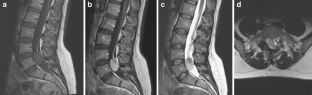

Fig. 2